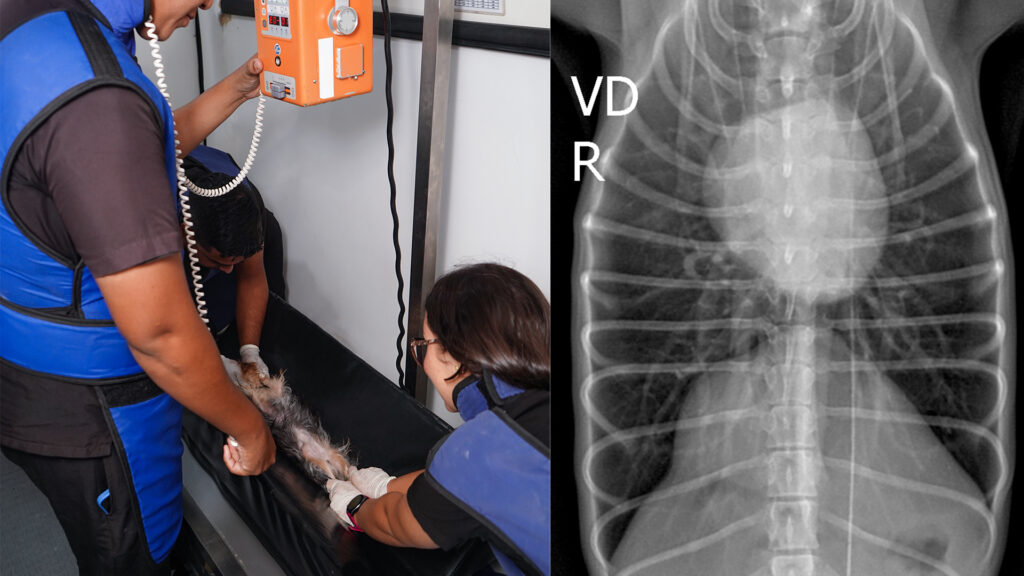

En 38 Plus Hospital Veterinario, contamos con un equipo de radiología de última generación para realizar estudios de rayos X. Esta técnica nos permite obtener imágenes detalladas del interior del cuerpo de tu mascota, facilitando el diagnóstico de diversas condiciones médicas.

- Evaluación de huesos y articulaciones: Identificación de fracturas, dislocaciones y enfermedades articulares.

- Examen de órganos internos: Diagnóstico de problemas cardíacos, pulmonares y abdominales.

- Detección de cuerpos extraños: Localización de objetos ingeridos o inhalados.